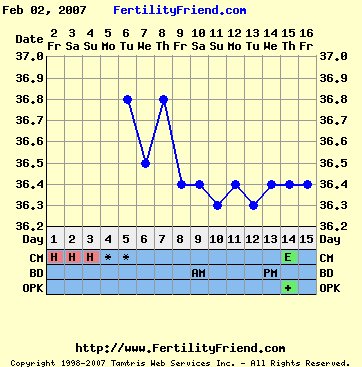

Képzeljétek, vettem megint LH tesztet, és ma pozitív lett, a hőm viszont még nem esett le. És megjelent a tojásfehérje is... nagyon kíváncsian várom a holnapi hőmet... lehet, hogy nem is fog leesni, hanem rögtön felugrik. De akkor is jó volt a tegnapi, és majd a holnapi együttlét is. Csak megjöjjön a pé vasárnapig. Hétfőn ugyanis utazik a párom! De addigra tuti meglesz.